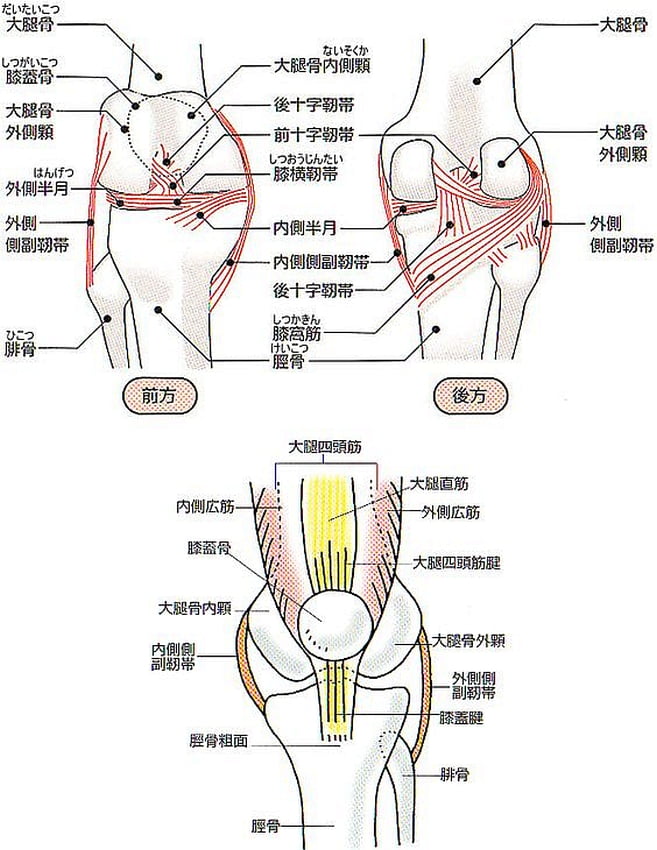

"皿"=膝蓋骨(しつがいこつ)以外の

自分の膝の箇所の骨が何処(半月?)か折れた

とも感じました。以下足の"膝部”の図解となります。

人間の膝というのは極めて複雑な組織で形成されています。